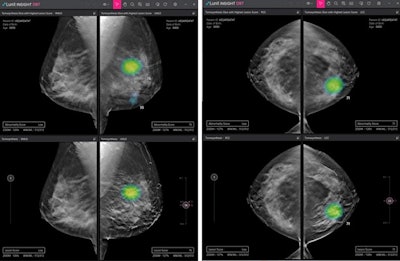

Lunit Insight DBT was designed to accelerate reading by identifying 3D slice images with suspicious breast lesions from among multiple images. Its new CT software is called Lunit Insight Chest CT, which automatically generates the location, type, volume, and axial diameter of detected nodules.

Lunit will offer demonstrations of Insight DBT and Lunit Insight Chest CT at the company's booth during the meeting, with an official launch planned next year, the company said.